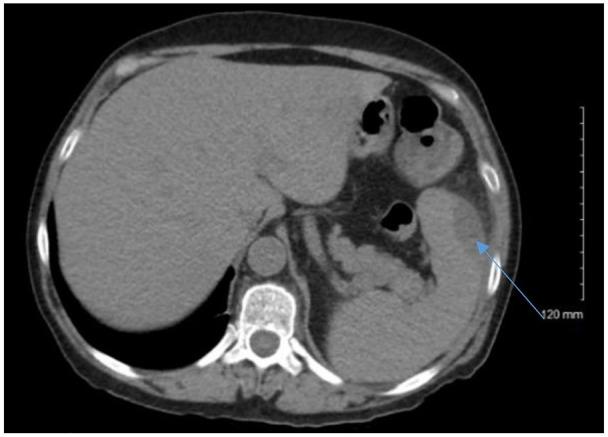

Splenic abscesses are a rare infection that usually requires seeding from another primary source; however, direct contact of bacteria can occur with microperforation secondary to colon cancer leading to abscess formation. This occurrence is rare, and through literature review only 12 previous cases have been reported with associated bacteremia. Our patient is a 62-year-old female who presented with left upper quadrant pain with a history of tobacco and alcohol abuse that was febrile and hypoxic. Blood cultures were obtained that eventually grew . Computed tomography of the abdomen and the pelvis revealed 2 splenic abscesses that were cultured to grow and β-hemolytic group C. Colonoscopy was performed, which identified 2 masses that were biopsied, and histopathology confirmed well-differentiated adenocarcinoma with possible muscular invasion. The patient had no other identifiable risk factors for bacterial seeding from another primary source. We present the first reported case report of splenic abscess secondary to colonic adenocarcinoma suspected microperforation associated with bacteremia.

脾脓肿是一种罕见的感染,通常需要从其他原发性疾病中接种细菌;然而,由于结肠癌导致的微小穿孔,细菌也可以直接接触,从而导致脓肿形成。这种情况很少见,通过文献回顾,只有 12 例先前报道的相关菌血症病例。我们的患者是一名 62 岁女性,有吸烟和饮酒史,表现为左上腹疼痛、发热和缺氧。随后进行了血培养,最终培养出 和 β-溶血性 C 群 。腹部和骨盆的计算机断层扫描显示有 2 个脾脓肿,培养出 和 β-溶血性 C 群 。进行了结肠镜检查,发现了 2 个肿块,并进行了活检,组织病理学证实为分化良好的腺癌,可能伴有肌肉浸润。患者没有其他可识别的细菌从其他原发性疾病接种的危险因素。我们报告首例疑似与 菌血症相关的结肠癌微小穿孔引起的脾脓肿病例。